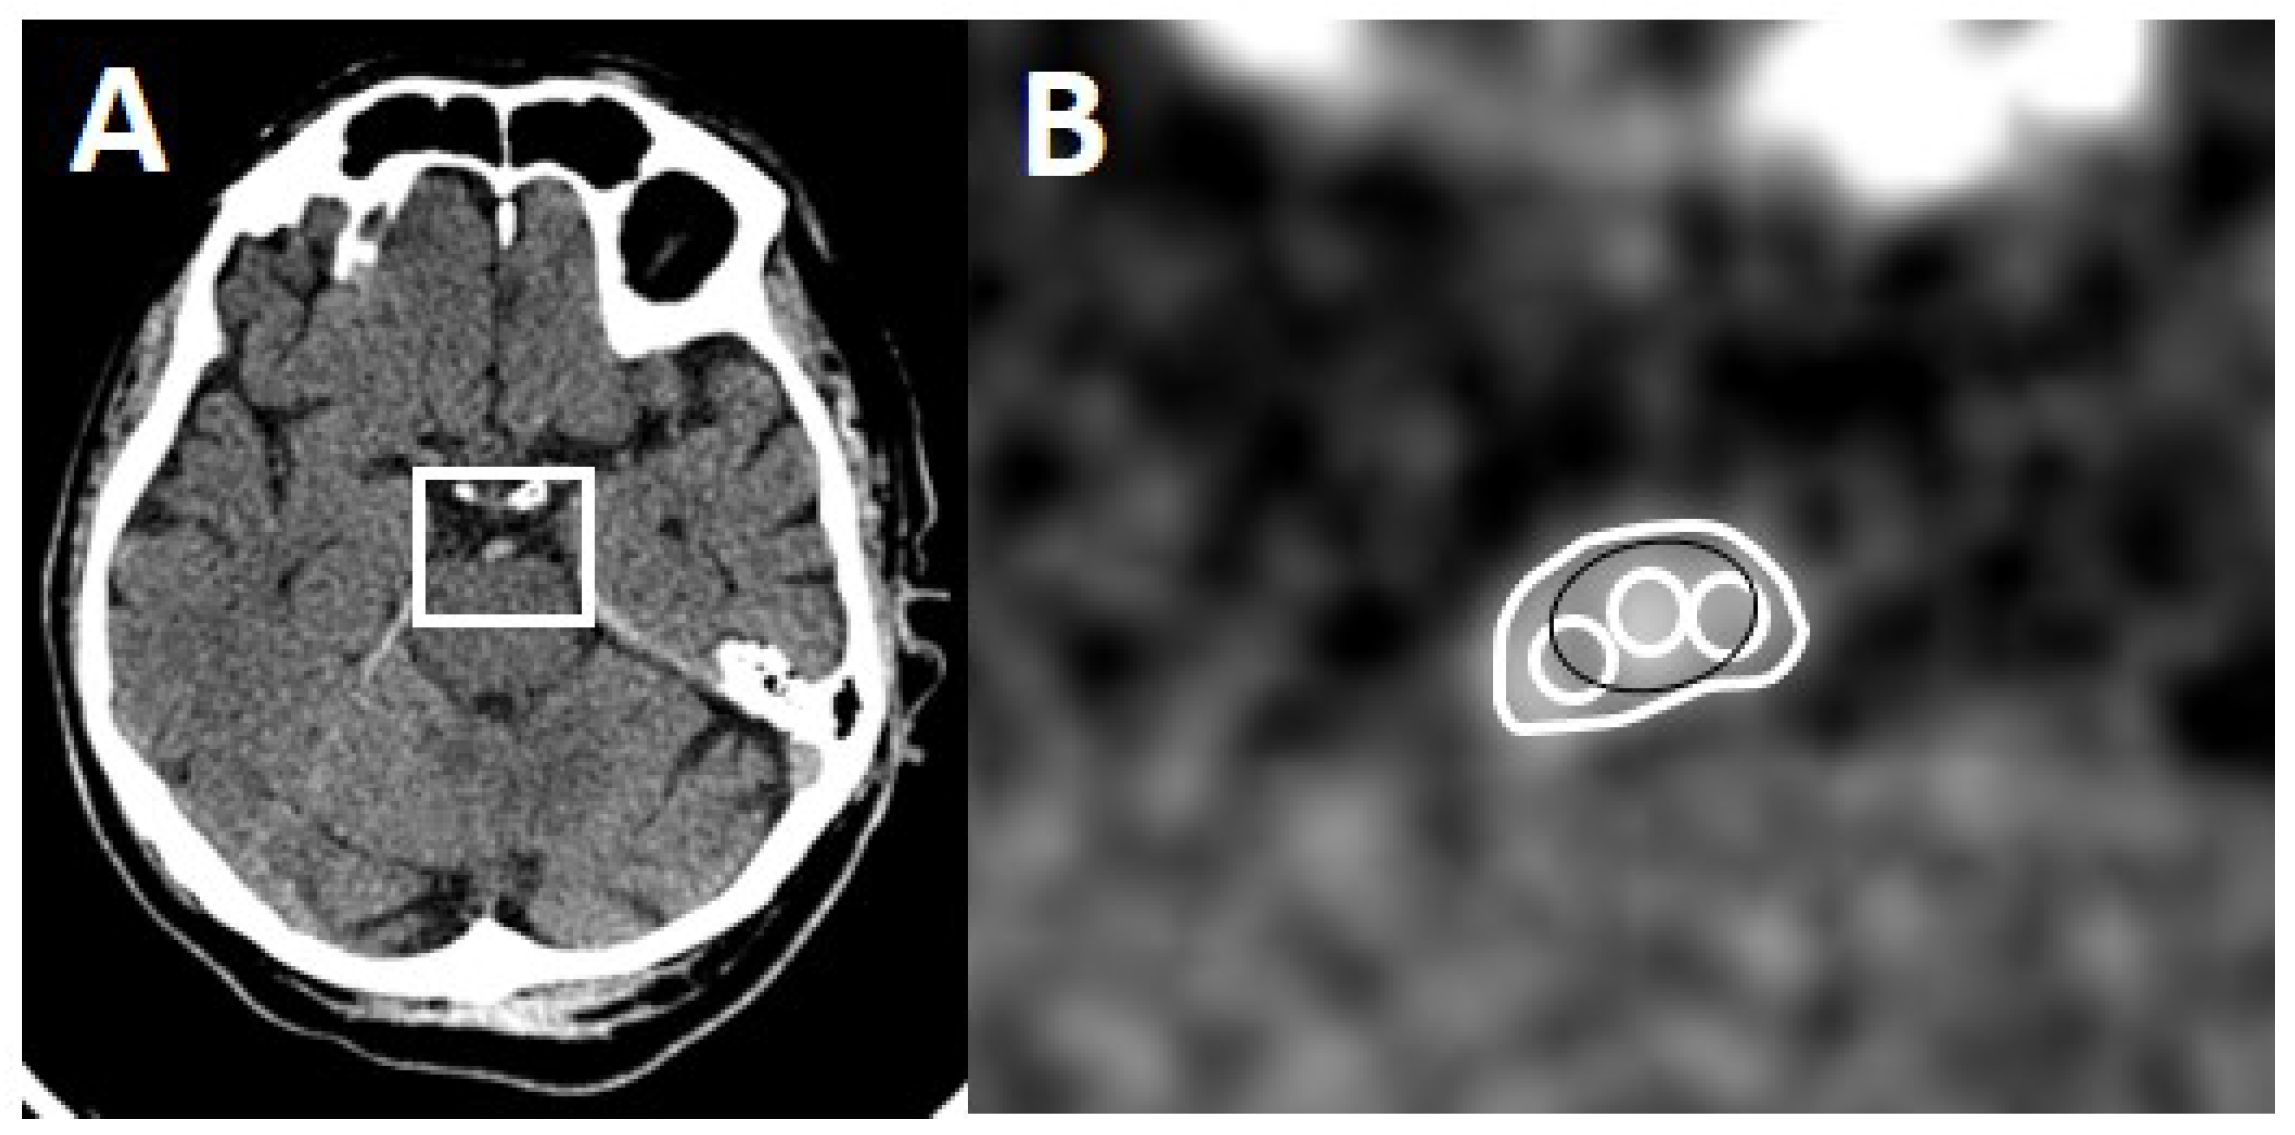

One rater (board-certified stroke neurologist) blinded to clinical and imaging results measured absolute thrombus density in all 56 patients on all NECCTs with all three available slice thicknesses (0.625, 2.5 and 5 mm). Three different methods were used. Method 1: one round or oval region of interest (RoI) was drawn onto the most hyperdense part of the thrombus [10]. Method 2: three small (or two if too small) oval or circular RoIs were drawn onto the thrombus [7]. Method 3: the outline of the whole thrombus was delineated by carefully excluding pixels outside the thrombus as a RoI on each slice of the NECCT [11]. For Method 2 and 3, the sum of the obtained density values was then divided by the number of drawn RoIs. Densities > 100 HU were considered calcifications and were excluded (Figure 1).

Figure 1.

Methods of thrombus delineation. (A) Axial CT section with a hyperdense basilar artery. (B) Magnified region of interest (white box) with the three methods of thrombus delineation. Method 1: black RoI, Method 2: three white circles, Method 3: large white RoI.